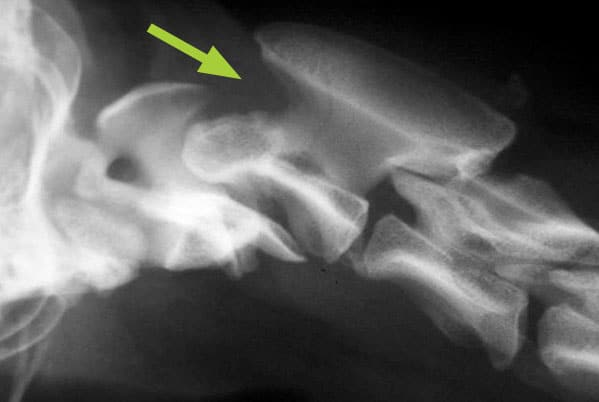

Flattening of the caudal humeral head (most common site)

due to Osteochrondritis Dissecans (OCD)

looks flatter bc cartilage is becoming thicker and thicker

will often be bilateral

large, fast growing dogs are predisposed